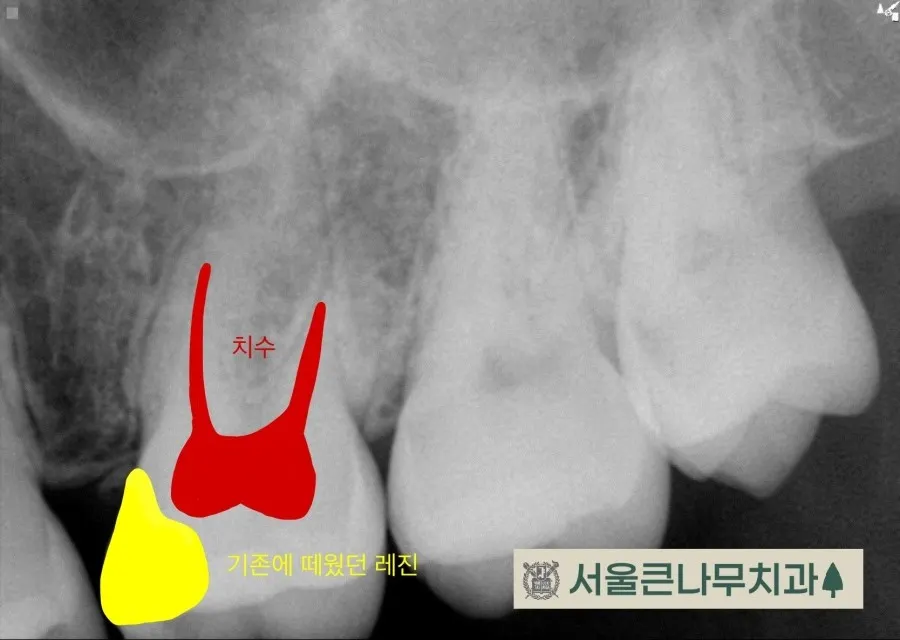

통증이 있는 치아에는 기존에 때웠던 레진 수복물이 있었고 겉보기에는 문제가 없어 보였지만,

자세한 진단을 위해 CBCT 촬영을 해본 결과, 동그라미 친 부위에 뿌리끝 염증이 발견되었습니다.

이전에 치료했던 레진 수복물이 치수에 가까워 신경에 영향을 주었을 것이라고 판단하고 신경치료에 들어갔습니다.

치아 안쪽을 열어본 결과 신경이 괴사되어 있었고 신경치료 후 환자분의 통증도 거짓말처럼 사라졌습니다.